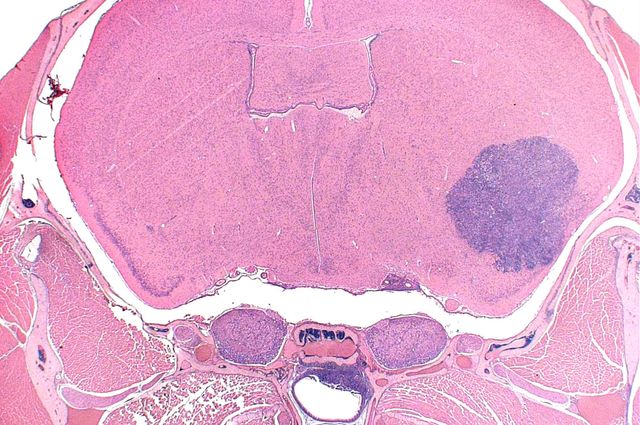

The rhabdoid tumor predisposition syndrome affects infants and toddlers who develop malignant, highly aggressive tumors mainly in the brain, spinal cord, kidney and other soft tissues. Treatment for rhabdoid tumors involves surgery and chemotherapy, but patients have a poor prognosis.

Giovannini and his colleagues used genetically modified mice to induce different gene mutations during development of rhabdoid and schwannoma tumors. The researchers also found that malignant tumors in this mouse model had very similar molecular features to human rhabdoid tumors.